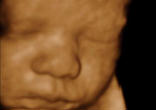

Fr. Pavone Presides over Funeral Service for Aborted Baby at National Event in Rochester

"We are holding this service in full view of the public. We are not ashamed of our youngest brothers and sisters, who continue to be ... continue reading